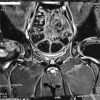

Subsequently, the patient was referred for a MRI examination with computed tomography (CT) correlation to further characterize the lesion. The lesion was well defined, lobulated with endosteal scalloping. It was heterogeneously hyperintense on T2W images, hypointense on T1W images, with slow progressive peripheral nodular enhancement in dynamic contrast-enhanced MRI (DCEMRI) curves, and area of cortical breach with extraosseous soft-tissue component (Fig. 2a, b, 3, 4). Few areas of diffusion restriction were noted within the lesion (Fig. 5).

In view of above findings, the radiological diagnosis of enchondroma with a pathological fracture was made. However, due to atypical presentation of the lesion (heterogeneous hyperintensity on T2W images, early progressive peripheral nodular enhancement, extraosseous soft-tissue component, and areas of diffusion restriction), a possibility of aggressive/ malignant etiology was also considered and, hence, a biopsy was performed. The biopsy demonstrated a hypocellular tumor composed of short spindle and stellate shaped tumor cells embedded on a markedly myxoid stroma without any chondroblasts or osteoclastic giant cells on HPE (Fig. 6a and b). Diagnosis of LGMFS was made. Immunohistochemistry was positive for smooth muscle antigen, vimentin and negative for synaptophysin-100, cluster of differentiation 34, desmin (Fig. 7a and b). MiB-1 labeling index was focally high (10–25%).